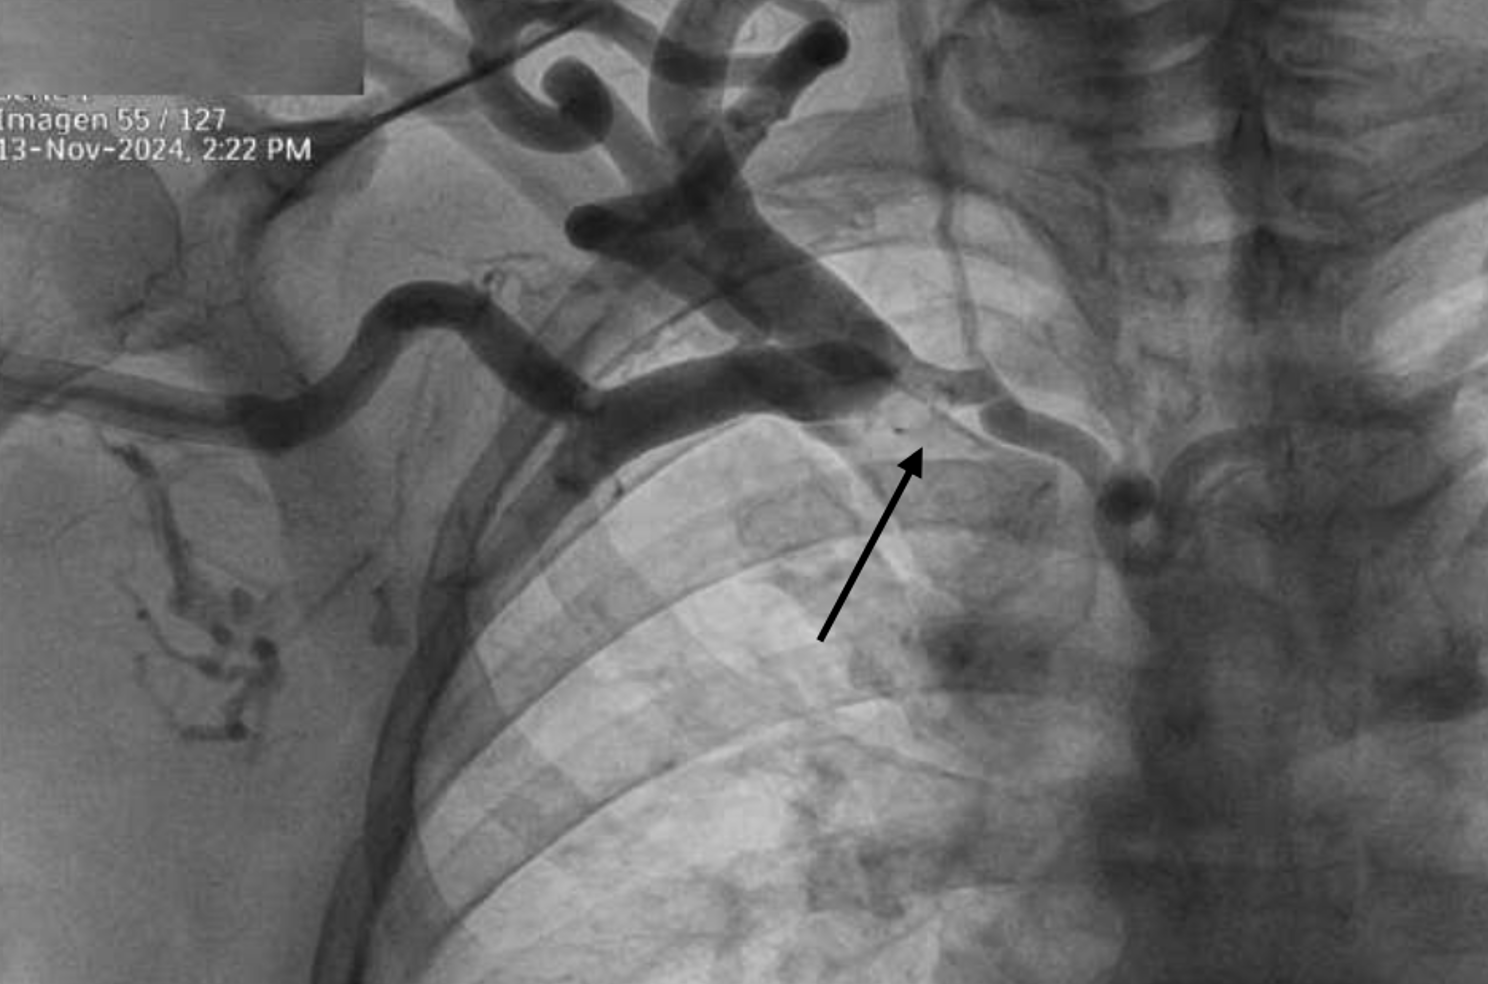

Perforation of the left innominate vein during placement of a hemodialysis catheter

Medical Image.

Luis Alvarez, Luis Alvarez (Author)

36-42